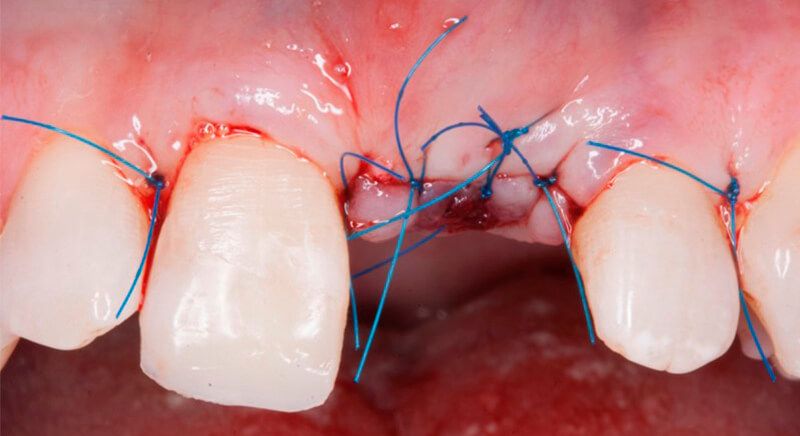

The socket was filled with a xenograft after the extraction and a graft of connective tissue was placed in the vestibular area of the two upper central incisors.

The tissue with epithelium was taken from the palate and de-epithelialized outside of the mouth. This obtains a lamina propria graft with better density and quality than if it were obtained with a single incision to the palate.